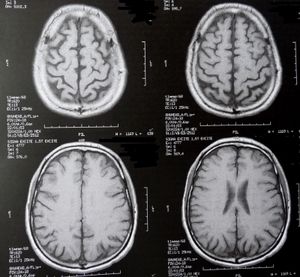

Gehirne: Gerät verlängert Leben, heilt aber nicht (Foto: pixelio.de, D. Schütz) |